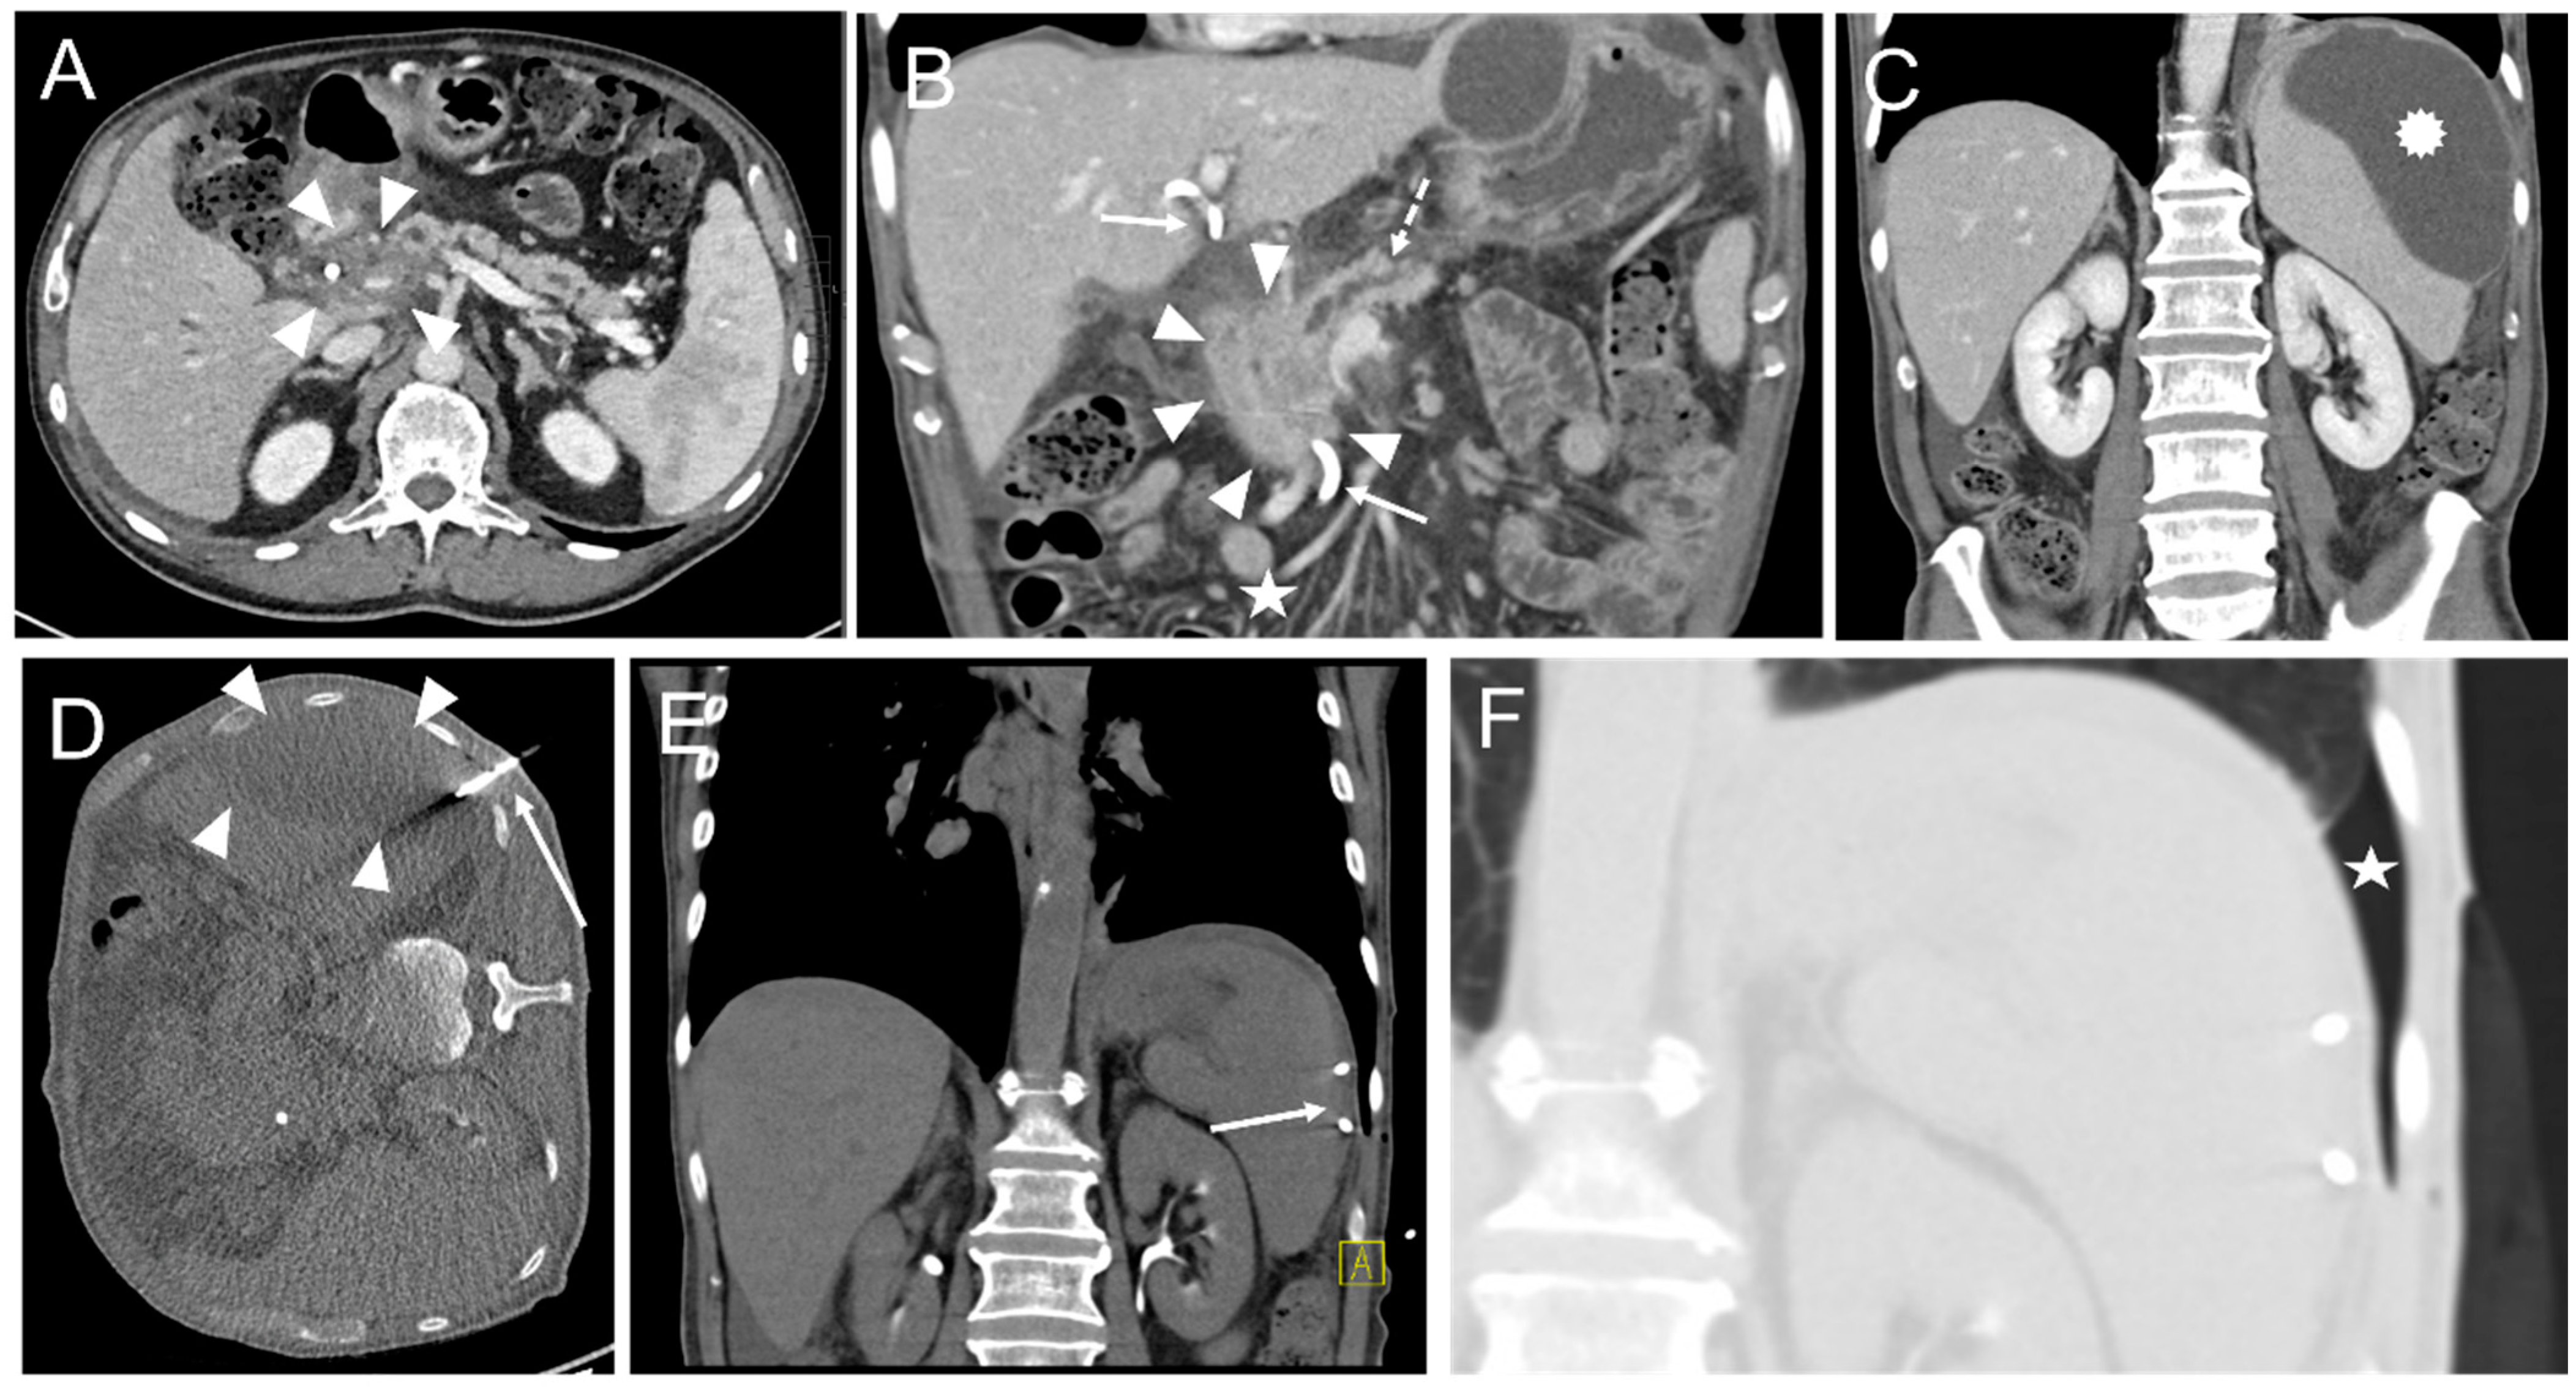

In one intervention, an instant replacement was necessary due to the dislocation of the initial drainage. In one case fluid collection was too small for drainage placement. Complications occurring during or immediately after the intervention were seen in three patients (1.8%). These comprised one major complication (according to SIR criteria) where operative revision was necessary (Table 4, Figure 3 and Figure 4).

Figure 3. An intervention with a minor complication according to SIR. (A) 70-year-old male developing jaundice. CT scan depicts a pancreatic head tumor (arrowheads) with infiltration of the hepatic artery and spread along the portal vein as well as the mesenteric root. (B) Infiltration and congestion of the pancreatic duct (dashed arrow), enlarged and roundly configured lymph node metastases (asterisk), and a previously endoscopically inserted drainage (arrows). Arrowheads: pancreatic head tumor. (C) An exploratory laparotomy including multiple biopsy samples of the pancreas was conducted. The Patient developed postoperative pancreatitis. Twenty-seven days after surgery a pancreatogenic, perisplenic subcapsular pseudocyst (star) was diagnosed on a CT scan. (D) Placement of an 8F drainage (arrow) within the fluid collection (arrowheads) in the right lateral decubitus position, guided by CT fluoroscopy. (E) Postinterventional unenhanced control CT scan shows the correct position of the drainage (arrow) and an almost complete disappearance of the fluid collection. (F) However, a small self-limiting pneumothorax (star) was observed in the lung window.